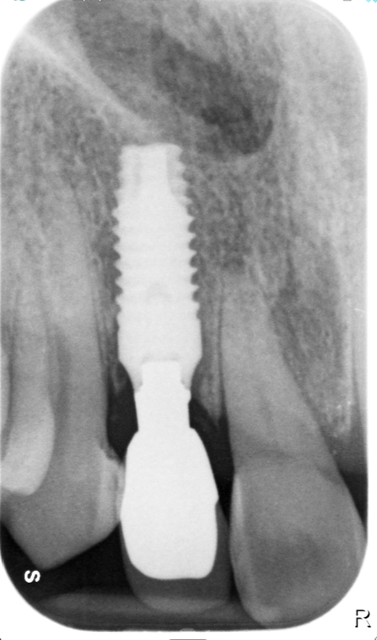

La morfologia convergente del collo Prama permette di recuperare la porzione di tessuto molle che con un impianto transmucoso tradizionale verrebbe occupata dal titanio del collo implantare. La convergenza di Prama fa sì che i volumi intorno alla porzione coronale dell’impianto vengano invece riempiti di coagulo e di importanti fattori di ricrescita, che si trasformano in tessuti molli spessi e funzionali.

L'ispessimento della gengiva che circonda il collo Prama rappresenta un beneficio indiscusso, soprattutto nei pazienti con biotipo più sottile, nei quali questo innovativo impianto apporta un ispessimento dei tessuti molli senza ricorrere a terapie rigenerative.

La stabilizzazione del connettivo, resa possibile dalla morfologia convergente e dalla microrigatura UTM, fa sì che tutto ciò che vi è al di sotto rimanga protetto e isolato da potenziali attacchi batterici, e che quindi l’osso si mantenga preservato in maniera efficace e a lungo, come ampiamente dimostrato dalla clinica.